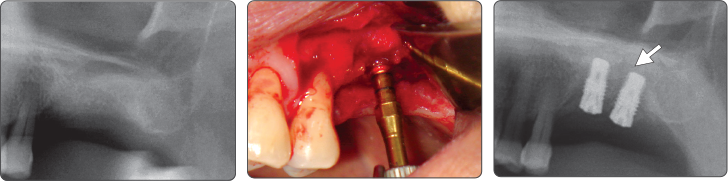

Sequence -Sinus Lift

▶ Immediate Implantation and Sinus Lift Technique with Tap Drill (Ø4.0 Fixture)

▶ Immediate Implantation and Sinus Lift Technique with Tap Drill (Ø5.0 Fixture)

- 提升上颌窦时,建议采用一起使用上颌窦提升钻和扩张钻的手术方式。